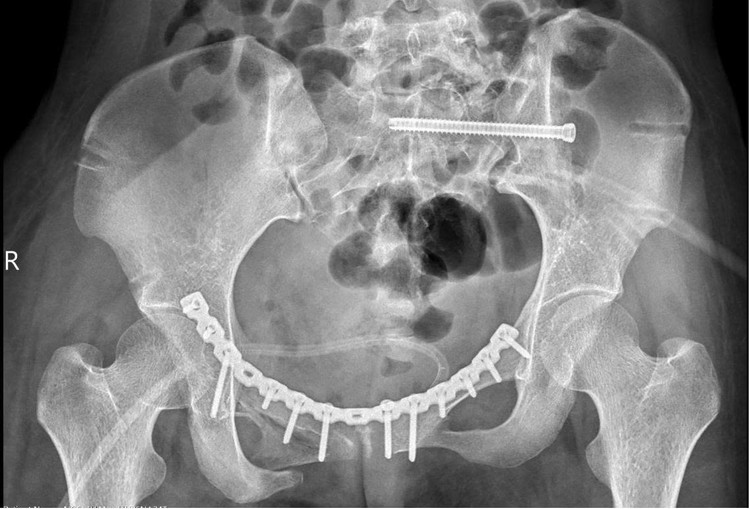

gay-xuong-chau-2.jpg

Hình ảnh xương chậu trên phim chụp sau nắn chỉnh - Ảnh BVCC

“Vì vậy, mục tiêu điều trị là phục hồi cấu trúc giải phẫu khung chậu và cố định vững chắc bằng nẹp vít, giúp bệnh nhân sớm vận động trở lại. Ở trường hợp này, khung chậu mất vững cả cung trước và sau, nên sau khi nắn chỉnh, chúng tôi cố định cung trước bằng nẹp vít và cung sau bằng vít xốp”, BS Khanh chia sẻ.